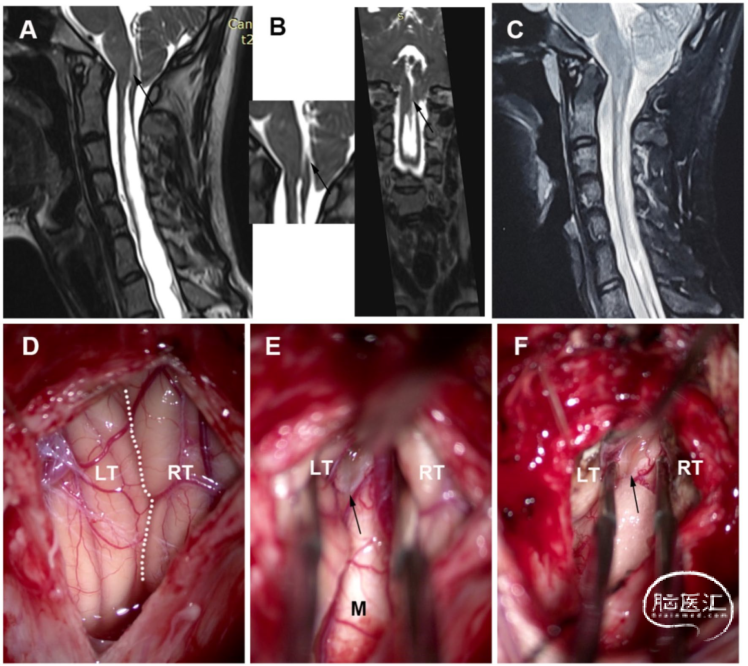

女性,72岁,有8年的四肢麻木和无力病史。术前MRI显示,髓内裂伴CM。术中可见萎缩的扁桃体占据枕骨大孔并覆盖在Magendie孔上。扁桃体低功率双极电凝烧灼后收缩复位,Magendie孔暴露,未观察到隔膜。但手术后症状并未缓解(图5)。

图5. 萎缩型CM-SM病例。A. 术前MRI显示,髓内裂伴CM-I。B. 术后MRI显示,SM的大小保持稳定。C. 打开硬脑膜后,见扁桃体萎缩,占据枕骨大孔和覆盖Magendie孔。D. 扁桃体低功率双极电凝烧灼后收缩复位,Magendie孔暴露,未观察到隔膜。